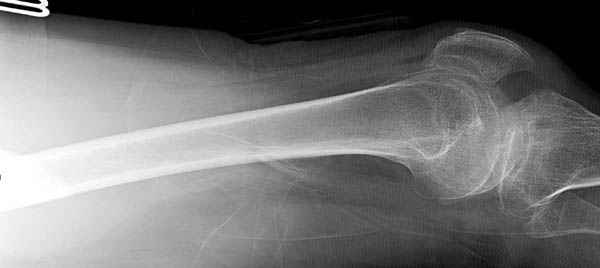

Среди русскоговорящих коллег Ортофорум стал одним из мест, где многие из нас черпают знания для решения своих ежедневных проблем в виде практических советов и обмена опытом. Кроме таких советов, Ортофорум стал источником новых познаний среди ортопедов, особенно по редко встречающимся состояниям в ортопедии. Продолжая традицию, я хотел бы представить редко встречающий случай перелома бедра у больного с гемофилией. Больному 42, гемофилия типа А, из истории упал с высоты около 1,5 метра, переправлен из другой больницы. По происхождению мексиканец, 10 лет назад по поводу артроза пр. коленного сустава в Мексике сделано протезирование, которое закончилось ампутацией выше коленного сустава. При поступлении бедро напряженное, сосудистых и неврологических расстройств нет. На рентгенограмме оскольчатый перелом бедра с вовлечением проксимальной спирали в шейку бедра. Хотели бы знать тактику ведения подобных больных и на что надо обратить внимание? Djoldas Kuldjanov, MD Department of Orthopedic Surgery St. Louis University Medical Center

Кровотечение удалось контролировать, и больной через пару дней выписан на амбулаторное лечение.